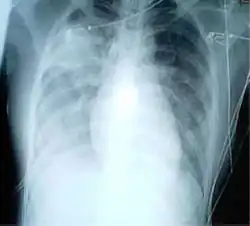

- Heart failure

Chest radiographs are used to diagnose many conditions involving the chest wall, including its bones, and also structures contained within the thoracic cavity including the lungs, heart, and great vessels. Pneumonia and congestive heart failure are very commonly diagnosed by chest radiograph. Chest radiographs are also used to screen for job-related lung disease in industries such as mining where workers are exposed to dust.[3]

Fluid in space between the lung and the chest wall is termed a pleural effusion. There needs to be at least 75 mL of pleural fluid in order to blunt the costophrenic angle on the lateral chest radiograph and 200 mL of pleural fluid in order to blunt the costophrenic angle on the posteroanterior chest radiograph. On a lateral decubitus, amounts as small as 50ml of fluid are possible. Pleural effusions typically have a meniscus visible on an erect chest radiograph, but loculated effusions (as occur with an empyema) may have a lenticular shape (the fluid making an obtuse angle with the chest wall).

Pleural thickening may cause blunting of the costophrenic angle, but is distinguished from pleural fluid by the fact that it occurs as a linear shadow ascending vertically and clinging to the ribs.